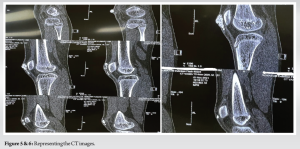

AP and lateral radiographs show cobblestone appearing calcific mass extending from superior aspect of patella extending to the inferior aspect along the pre-patellar region. Intra-articular calcific mass was also found on the radiograph with connection the major mass. Computer Tomography scan was done which confirmed the tumoral calcinosis along the pre-patellar region and a separate intra-articular calcific mass. Complete blood count was found within normal limits, serum calcium, phosphate, alkaline phosphatase, uric acid, and Vitamin D levels were found to be in the normal range when metabolic profile was done (Fig. 3-6).

Tumoral calcinosis has a typical appearance on radiographs: amorphous, cystic, and multilobulated calcification located in a periarticular distribution. Axial CT better delineates the calcific mass. The cystic appearance shows fluid-fluid levels caused by calcium layering and commonly termed the sedimentation sign [19]. However, the lesion may appear homogeneous, suggesting a reduced metabolic activity and a lower likelihood of growth. Erosion or osseous destruction by adjacent soft-tissue masses is absent, another distinguishing finding of tumoral calcinosis. MR imaging with T2-weighted sequences generally shows inhomogeneous high signal intensity even though there is a large amount of calcification [20]. Histopathologic features of tumoral calcinosis. (a) High-power light microscopy shows a calcified mass in the center of the field with foreign body inflammatory reaction, giant cells, and surrounding fibrosis. (b) Low-power light microscopy shows several calcified masses with chronic inflammatory and fibrotic encapsulation. Tumoral calcinosis usually represents soft-tissue neoplasm as is with the index case described above. High index of suspicion is needed along with consideration of alternate diagnosis should be done. The disorders mimicking tumoral calcinosis are calcinosis of chronic renal failure, calcinosis universalis, calcinosis circumscripta, calcific tendonitis, synovial osteochondromatosis, synovial sarcoma, osteosarcoma, myositis ossificans, tophaceous gout, and calcific myonecrosis. Surgical excision is the treatment modality of choice for tumoral calcinosis. Recurrences are common due to poor circumscription, especially when it is actively progressing. Phosphate depletion in both normo- and hyperphosphatemia has proved to have variable success. Resistant cases are thought to be related to a late-stage tumoral calcinosis lesion surrounded by an impeding fibrous layer that prevents ion exchange. However, surgical excision combined with phosphate deprivation (using aluminum hydroxide) in conjunction with acetazolamide synergistically lowers hyperphosphatemia and has proved to be the most effective therapy. Other therapies, including systemic steroid therapy and radiation therapy, have not been proved to be effective [21,22].